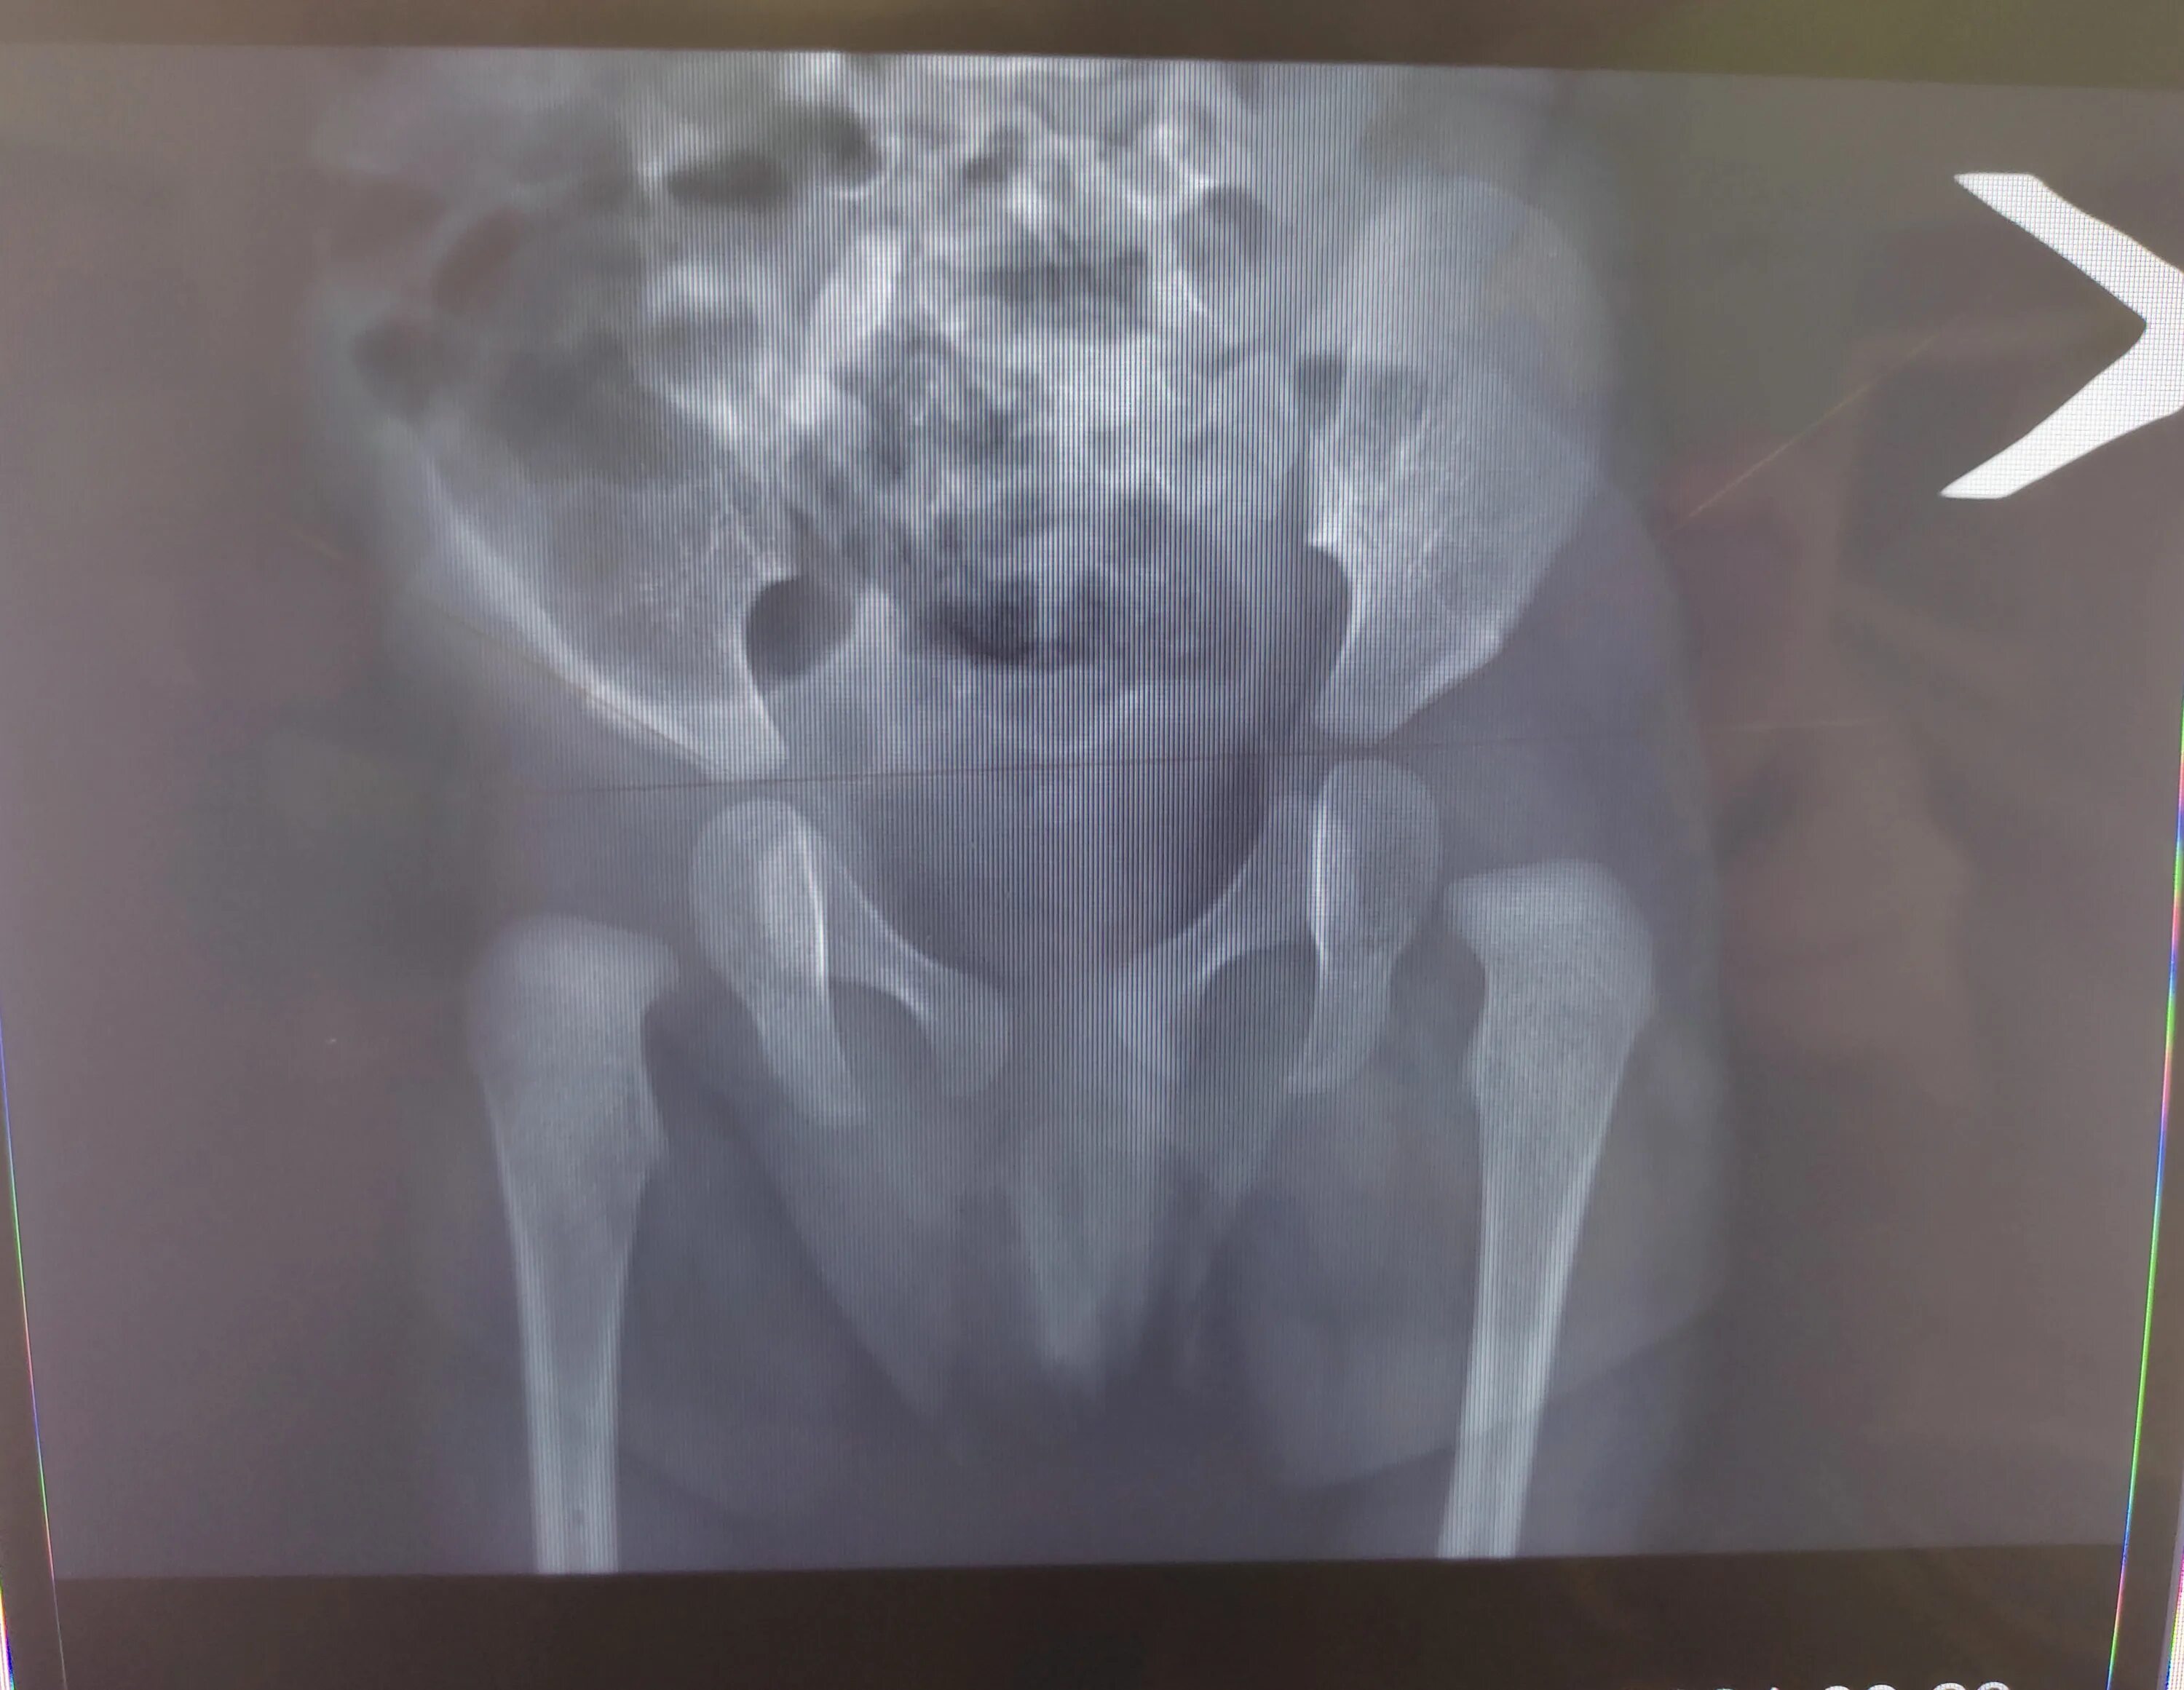

Мкб дисплазия тазобедренных суставов детей